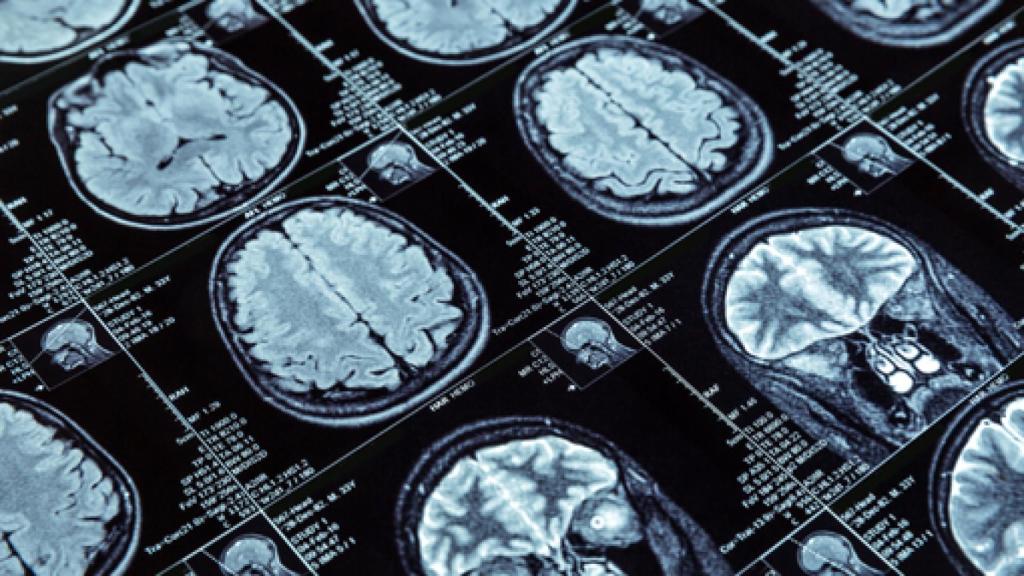

Imagen de una resonancia magnética actual

Sánchez Ron aborda las técnicas de imagen en medicina a propósito de la reciente muerte de Sir Peter Mansfield, Premio Nobel de Medicina por sus descubrimientos relativos a la obtención de imágenes mediante resonancia magnética. Otro protagonista es el médico Raymond Damadian.

El 18 de febrero falleció Sir Peter Mansfield (1933-2017), el físico británico que recibió en 2003, junto al químico estadounidense Paul Lauterbur (1929-2007), el Premio Nobel de Medicina "por sus descubrimientos relativos a la obtención de imágenes mediante resonancia magnética". La importancia de los métodos de imagen en la medicina actual, bien merece que dedique un recuerdo a este tipo de logros.